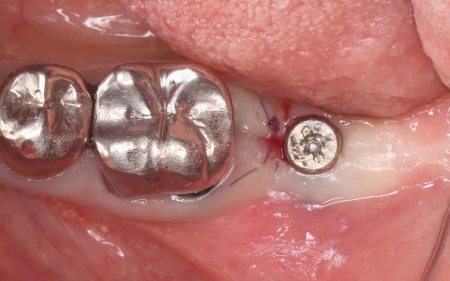

まずは局所麻酔を行い、破折した歯を丁寧に抜きます。

その後、歯科用CT撮影を行い、顎の骨の量や形、神経や血管の位置を立体的に確認しました。撮影したデータをもとに、インプラントを埋め込む位置や角度、深さについて事前に設計を行い、安全性と噛み合わせのバランスを考慮した治療計画を立てます。

抜歯後は骨の治癒を待つため、約3ヶ月間の経過観察を行いました。

歯根破折が疑われました。

抜歯後の骨の状態を確認しています。